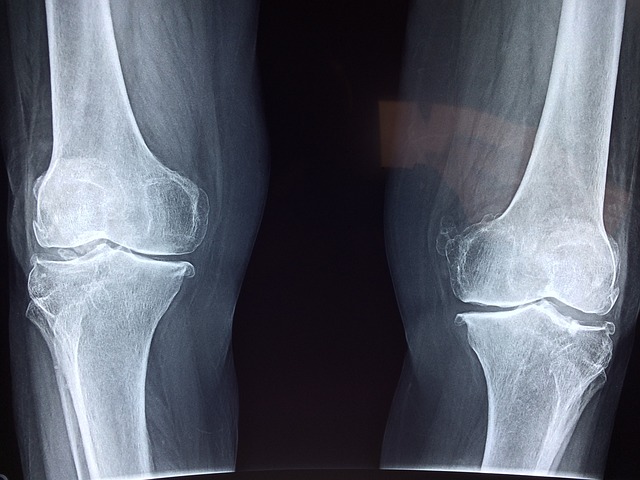

- 프로테오글리칸의 효능 중 제일 우리 몸에 좋은 효능은 바로 관절과 연골에 많은 개선점을 준다는 것입니다. 프로테오글리칸은 연골 내에서 주고 발견이 되는데 이러한 연골의 유연성과 강도를 유지하는데 큰 역할을 합니다. 만약 프로테오글리칸이 부족하게 된다면 관절염과 연골질환과 같은 다양한 질병에 노출될 수 있기 때문에 반드시 필요한 요소라고 볼 수 있습니다.

- 위에서 언급한 대로 프로테오글리칸은 연골, 피부, 혈관 등에서 발견되는 성분입니다. 이러한 조직의 유연성을 유지해 주고 외부로부터 충격을 보호해 주는 역할을 합니다. 이러한 충격을 흡수함으로써 관절을 보호하고 관절 건강을 지속적으로 유지할 수 있게 도와줍니다.

- 우리 몸의 뼈는 단단한 섬유질과 무기질 성분인 하이드록시아파타이트로 이루어져 있는데 프로테오글리칸이 어린 뼈조직에 있는 칼슘과 다른 무기질을 조절함으로써 뼈를 튼튼하게 만드는데 큰 도움을 줍니다. 또한 세포 간의 신호전달에 큰 기여를 하여 뼈의 대사를 조절하는데 이로 인해 뼈조직을 더욱 튼튼하게 하여 골다공증을 예방하는데 큰 역할을 합니다.